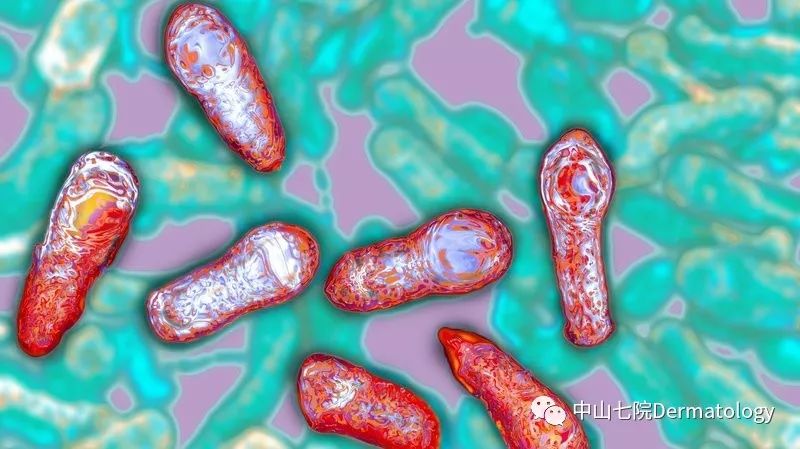

肉毒素,本质是一种细菌(肉毒梭状芽孢杆菌)产生的毒素。当然,我们将其作为药物使用还是经历了分离,纯化等多种步骤。不同的菌株会产生不同种类的肉毒素,我国食品药品监督局仅批准了一种肉毒素(A型肉毒素)作为临床使用药物。

显微镜下肉毒梭状芽孢杆菌本尊